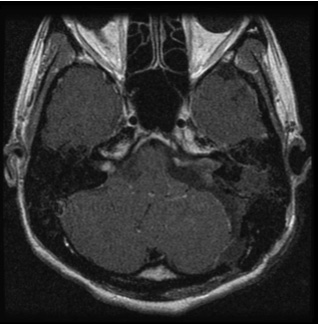

図1:20代男性 聴神経腫瘍

(左図)術前MRI:術前聴力は10dB

(右図)術後MRI:内耳道に筋肉片がおかれている術後聴力は温存16dB 顔面麻痺はなし